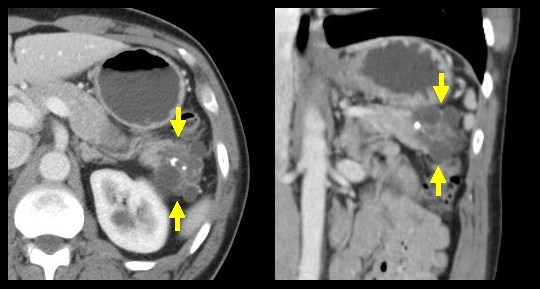

胰腺浆液性囊腺瘤(寡囊型) ct74胰腺颈部见囊性肿物影,其内可见